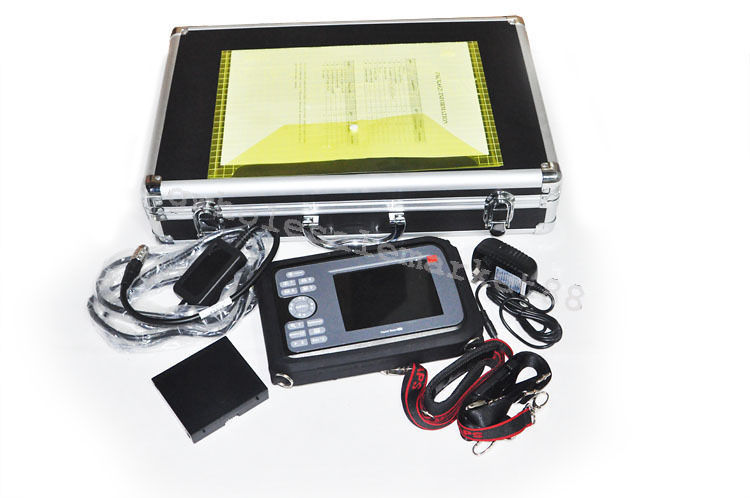

Portability and User-Friendly Interface

One of the standout features of this laptop ultrasound scanner is its portability. Weighing less than conventional ultrasound machines, it allows healthcare professionals to bring it right to the patient’s side. Plus, the user-friendly interface simplifies the operation, making it suitable for medical staff of all experience levels. Also, the compact size ensures that it fits easily into tighter spaces, such as small clinics or in-home care environments.